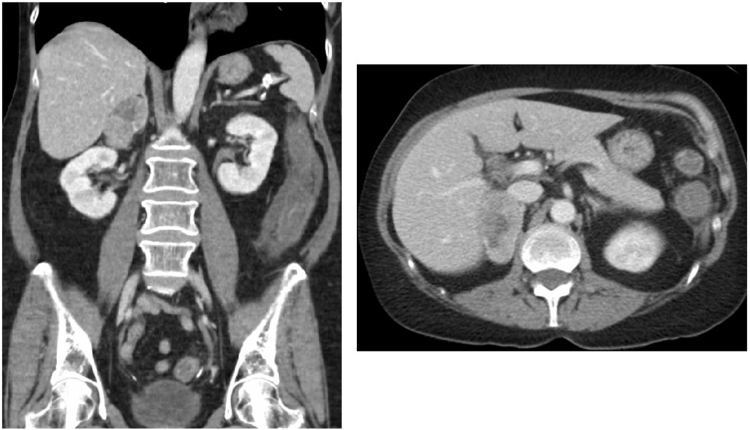

A 70-year-old woman presented with abdominal pain and was found to have a large right adrenal mass and hypercortisolism. Right adrenalectomy was pursued with pathology consistent with diagnosis of ACC. Three months after surgery, hypercortisolemia recurred and bony metastatic disease was detected soon after. The patient received chemotherapy and mitotane; however, mitotane was stopped after development of hemolytic anemia. The patient’s urinary free cortisol became severely elevated, and osilodrostat was subsequently initiated for steroidogenesis inhibition. As dosage was increased, the patient presented with fatigue and hypotension and was diagnosed with adrenal insufficiency. This was managed with hydrocortisone in a block-and-replace dosing strategy.